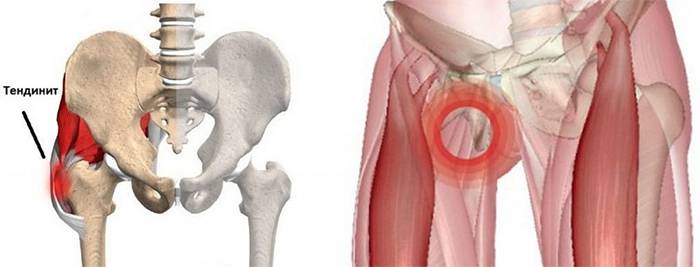

Здоровье суставов: Трохантерит и его влияние на мышцы